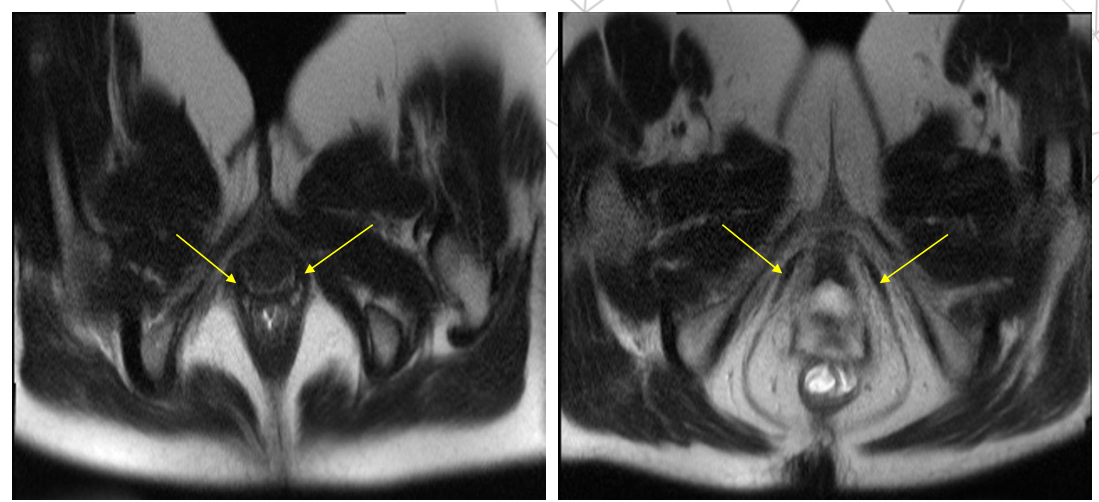

T2 HASTE VALSAVA

T: thì nghỉ

P: thì rặn

T2 TRUEFISP cor, ghi hình CINE